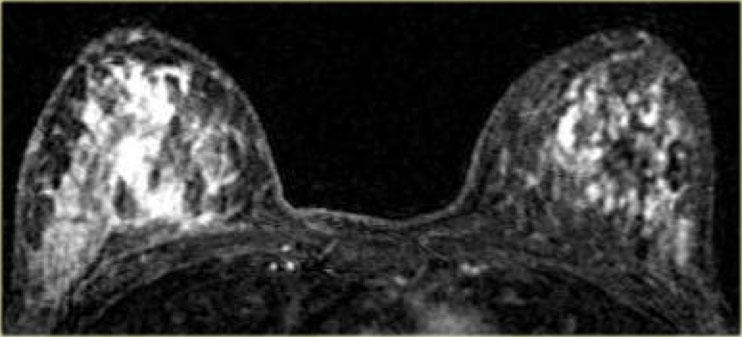

Bên trái là một trường hợp khác với DCIS lan tỏa hai bên.

Một trường hợp DCIS khác, khu trú ở phía ngoài cả hai vú.

Các trường hợp bên trái khó chẩn đoán hơn.

Cả hai bệnh nhân này đều có các vùng ngấm thuốc đồng nhất rộng ở vú phải.

Ở cả hai bệnh nhân, kết quả được xác định là DCIS.